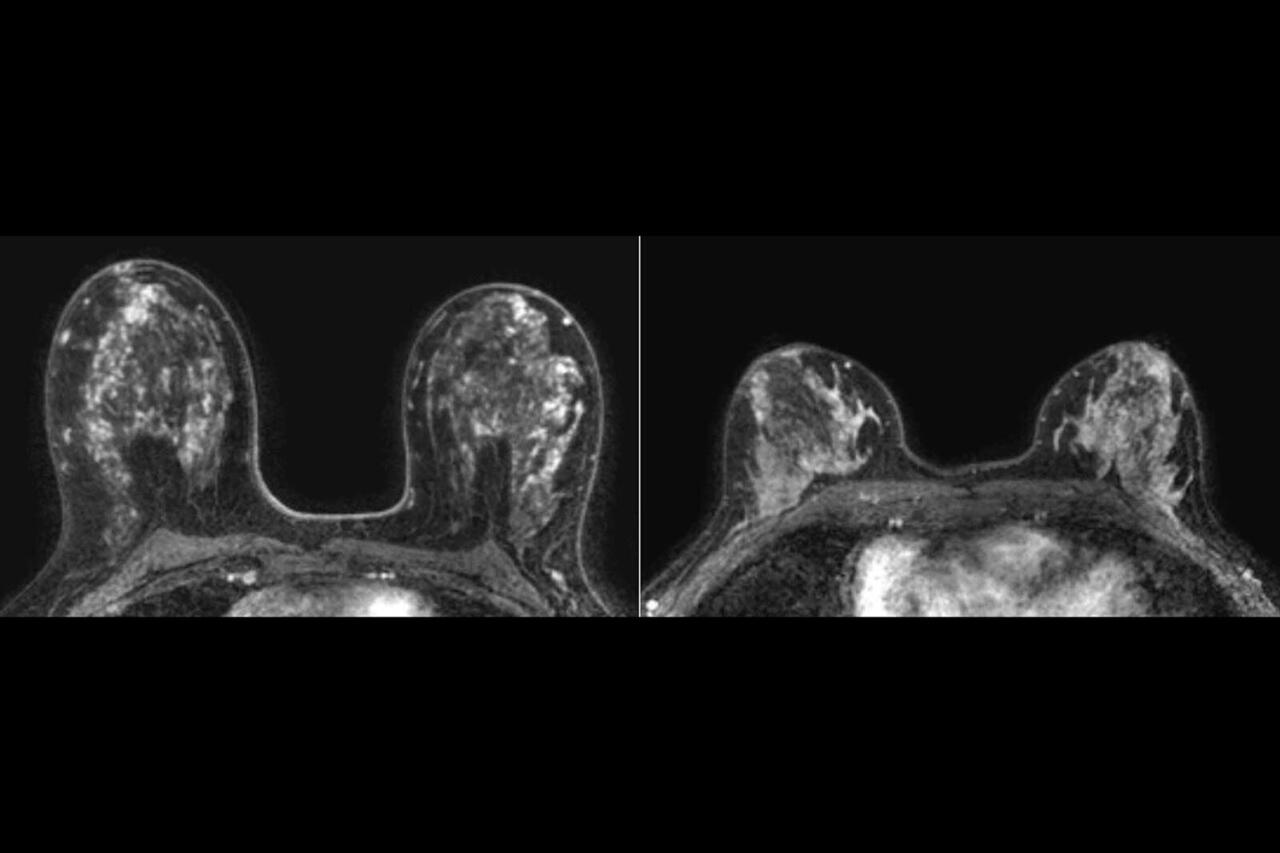

В экспериментах на мышиных моделях и клетках рака молочной железы человека ученые выяснили, что присутствие бактерии ускоряет рост опухоли и усиливает распространение раковых клеток в легкие. При локальном воздействии в тканях молочной железы возникали гиперпластические и метапластические изменения - это нераковые состояния, при которых клетки либо чрезмерно делятся, либо меняют свой тип. Такие процессы сопровождались воспалением и повреждением ДНК.